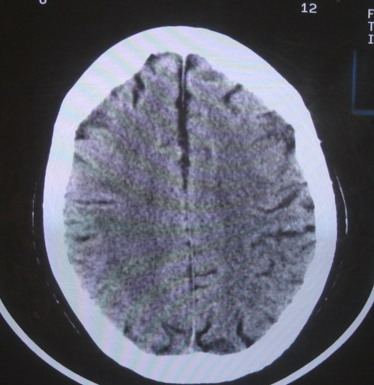

女  67岁 双下肢无力,行动不灵便

老年脑

脑萎缩,腔隙性脑梗塞.

双侧额桥束及左侧脑室旁多发腔梗塞+老年性脑改变

多发腔梗、老年性脑改变、脑白质异常。